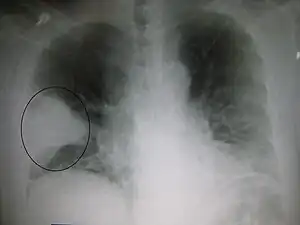

![]() O radiografie alb-negru a pieptului care arată o suprafață triunghiulară albă în partea stângă. Un cerc marchează suprafața. | |

Radiografia toracică este frecvent utilizată în stabilirea unui diagnostic.[14] La persoanele cu forme mai ușoare, radiografia este necesară numai în cazul celor cu posibile complicații, celor care nu răspund la tratament, sau atunci când cauza este incertă.[14][41] Dacă o persoană este atât de bolnavă încât necesită spitalizarea, se recomandă o radiografie toracică.[41] Rezultatele nu indică întotdeauna severitatea bolii și nu deosebesc cu siguranță între infecțiile bacteriene și cele virale.[14]

Radiografiile pot clasifica pneumonia drept pneumonie lobară, bronhopneumonie (cunoscută drept pneumonie lobulară), și pneumonie interstițială.[44] Pneumonia bacteriană, existentă în comunitate, prezintă de regulă consolidarea pulmonară a unui lob pulmonar, fiind cunoscută drept pneumonie lobară.[24] Cu toate acestea, rezultatele pot varia, iar alte caracteristici sunt obișnuite în alte tipuri de pneumonie.[24] Pneumonia de aspirație poate prezenta opacități bilaterale mai ales la baza plămânilor și pe partea dreaptă.[24] Este posibil ca în unele cazuri radiografiile pneumoniei virale să pară normale, să aibă un aspect hiper-inflamat sau să pară similare pneumoniei bacteriene cu consolidare lobară.[24] Este posibil ca în stadiile incipiente ale bolii să nu existe semne depistabile radiologic, mai ales în cazul deshidratării; sau pot fi dificil de interpretat în cazul persoanelor obeze sau care au antecedente de afecțiuni pulmonare.[15] O tomografie computerizată poate oferi informații suplimentare în cazurile incerte.[24]